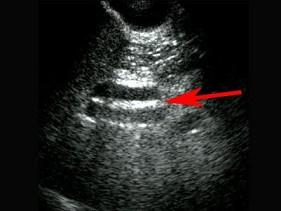

红色箭头所指部位是?(?)A.管环征B.滚石征C.双筒枪征D.米老鼠征E.飞鸟征

选项 A.管环征 B.滚石征 C.双筒枪征 D.米老鼠征 E.飞鸟征

答案 A